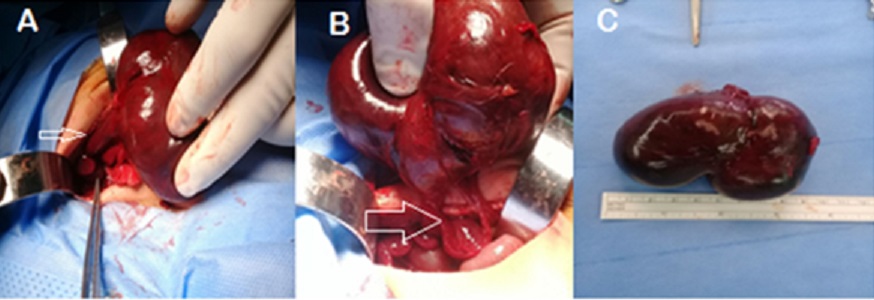

Due to the worsening of clinical status and fearing an abdominal compartment syndrome, laparotomy was performed through a right supra umbilical abdominal incision. A huge mass was found arising from the under surface of the right lobe of the liver with a pedunculated vascular connection extended across the plane of the falciform ligament (Fig.2A, 2B). The consistency of the mass was soft to firm. The mass was excised with ligation of tumor pedicle, and preservation of hepatic tissue. The tumor size was more than 9cm and weighed 125grams (Fig.2C). Postoperatively the baby was ventilated for two more days and later had a smooth postoperative recovery. Feeding was established fully by the third postoperative day. All postoperative laboratory tests were within the normal range.

Fig.2

Intraoperative finding of giant pedunculated hepatic hemangioma. A) Arrow pointed to the tumor pedicle. B) Excision of the tumor with preservation of liver tissue,the arrow pointed to the tissue of the right hepatic lobe.C)The excised tumor was.